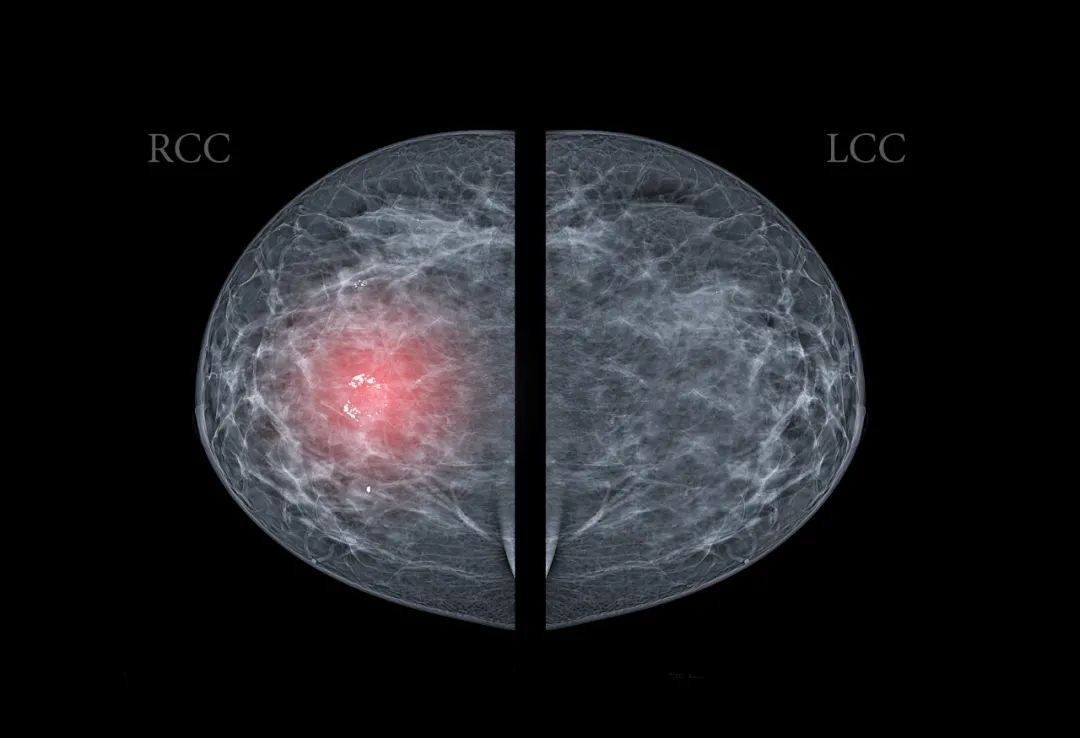

乳腺癌转移案例

夏女士(化名),4 个月前偶然发现左侧乳腺有包块,无疼痛、发热等症状。没太在意,但随着时间推移,包块越长越大,夏女士这才去医院,结果被诊断为「左侧乳腺癌」。为进一步评估全身转移情况,我们为夏女士进行了 PET/CT 检查。

影像:

左乳软组织肿块伴坏死,FDG 代谢活跃

诊断:

考虑乳腺癌,伴左乳头侵犯,左侧胸大肌受累可能;并伴:(1)左侧腋窝淋巴结转移;(2)双肺转移瘤。